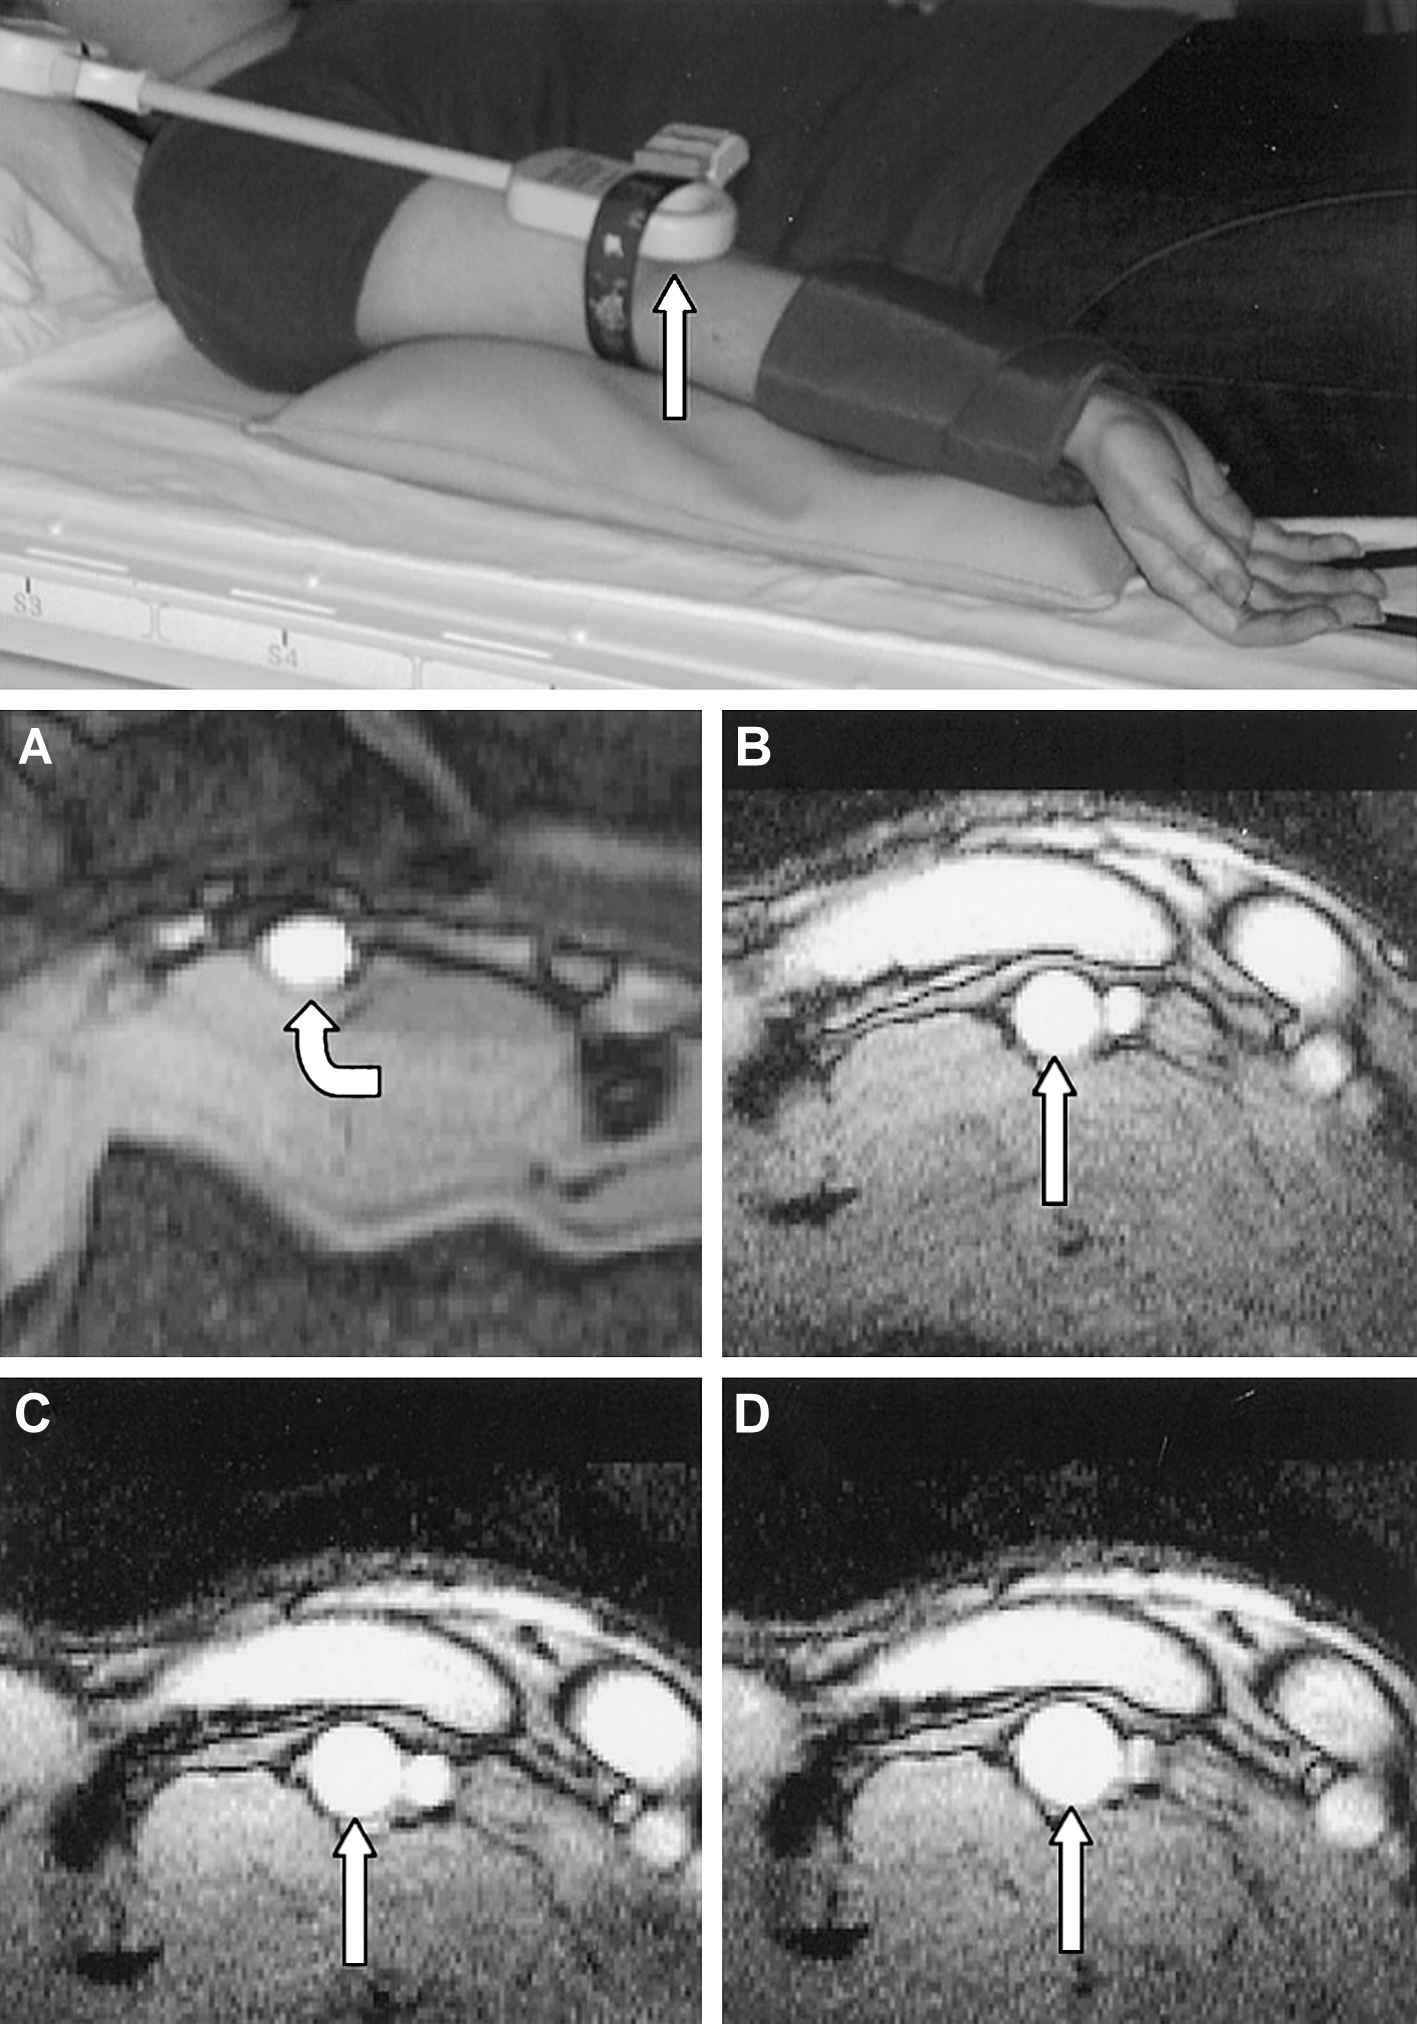

The endothelial layer of the vessel wall plays a central role in vascular homeostasis. This includes the regulation of the vascular tone by endothelium-derived relaxing and contracting factors, as well as important effects on vascular inflammation, leukocyte adherence, mitogenesis, platelet activation, thrombosis and thrombolysis.1 Usually vasomotor function is used for assessing endothelial function as introduced for ultrasound by Celermajer et al. in 1992.2 The first MRI-based study on vasomotor function was published by Sorensen et al. in 2002.3 They used an identical setting as published by Celermajer et al., but employed high resolution MRI instead of ultrasound to assess flow mediated dilation (FMD) in the brachial artery (see Fig. 2). The use of a small surface coil and a segmented FLASH gradient echo sequence resulted in a pixel size of 0.27 × 0.27 mm and an acquisition time of 12 cardiac cycles. Measurements correlated well to intravascular ultrasound (IVUS) (r = 0.87, p < 0.01) and the interstudy reproducibility was significantly better for MRI. The most probable reasons for the improved reproducibility are that MRI is less operator dependent and truly cross sectional views of the vessel permit more accurate measurement. The lower interstudy variability allows for smaller sample sizes in controlled trials using FMD-related endpoints. MRI of FMD, however, is subjected to the same shortcomings as ultrasound: brachial artery dilation is dependent on shear stress and peripheral resistance, which are both influenced by interfering variables such as age, gender, hypertension and other risk factors.4 This problem was addressed by Silber et al. who implemented phase contrast magnetic resonance imaging to assess endothelial function.5 Using sequences with high temporal and spatial resolution they obtained a cross sectional flow map of a conduit artery. In each pixel, the peak flow velocity was determined. From the distribution of the peak flow velocities the radius of the vessel as well as the shear rate at the vessel wall can be calculated. FMD assessed with this method was well correlated to FMD assessed with ultrasound, but again interscan variability of CMR was smaller.6 The other advantage of this CMR approach is the possibility to simultaneously assess shear stress, which is the responsible variable for endothelial NO release and vasodilatation. This offers additional insights in interpreting FMD. Thus, Silber et al. were able to identify shear stress as a possible explanation for the greater FMD seen in smaller vessels.7 A limitation of this approach is, however, that it uses systolic peak flow, whereas the guidelines for FMD recommend diastolic assessment of vessel diameter.8

Use of a small surface coil in the set-up for assessing flow mediated dilation (FMD) by CMR (upper image). Baseline image of a brachial artery with an oval shape (A). (B–D): series of images in a healthy subject at baseline (B), during reactive hyperemia (C) and after sublingual dose of GTN (D) (figure reprinted with permission from Sorensen et al.3).